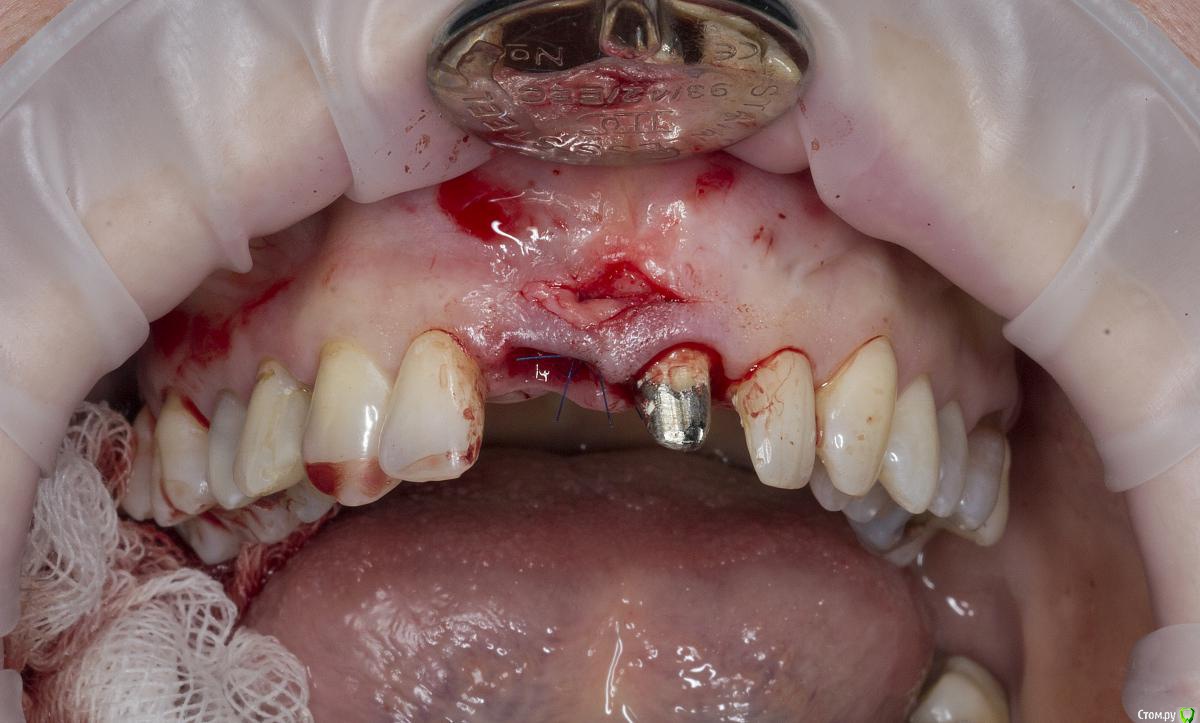

Александр07 Опубликовано 26 июня, 2020 Автор Поделиться Опубликовано 26 июня, 2020 Коллеги, скидываю фото проделанной работы, прошло около 1.5 мес, есть результат, спасибо за помощь, если какие то замечания /советы есть пишите 4 Ссылка на комментарий

колесников Опубликовано 26 июня, 2020 Поделиться Опубликовано 26 июня, 2020 (изменено) Здравствуйте! Не видел этого поста раньше,бегло посмотрел. Определенно проблема была в выборе высоты абатмент и объёме реставрации. Вы убрали композит максимально в основании-это хорошо,но абатмент оставили прежний. Следовало взять новый с высотой уступа 4-5 мм. Край коронки пришеечный следует опустить ниже,иначе десна опять отскочит. И переход слелайте на плавный а под углом,так называемый балкон. Потом будет что отдавить. По Масана сосочек сделали это хорошо и правильно,но с такой реставрацией опасно,мало место лоскуту. К счастью кажется все живы. На данном этапе рекомендую пропилить балкон и этим ограничится. Изменено 26 июня, 2020 пользователем колесников Ссылка на комментарий

Александр07 Опубликовано 27 июня, 2020 Автор Поделиться Опубликовано 27 июня, 2020 Справились одним трансплантом в итоге?)Два, один под сосочек с бугра второй вестибулярно с неба Сст 1 Ссылка на комментарий

Александр07 Опубликовано 27 июня, 2020 Автор Поделиться Опубликовано 27 июня, 2020 Здравствуйте! Не видел этого поста раньше,бегло посмотрел. Определенно проблема была в выборе высоты абатмент и объёме реставрации. Вы убрали композит максимально в основании-это хорошо,но абатмент оставили прежний. Следовало взять новый с высотой уступа 4-5 мм. Край коронки пришеечный следует опустить ниже,иначе десна опять отскочит. И переход слелайте на плавный а под углом,так называемый балкон. Потом будет что отдавить. По Масана сосочек сделали это хорошо и правильно,но с такой реставрацией опасно,мало место лоскуту. К счастью кажется все живы. На данном этапе рекомендую пропилить балкон и этим ограничится.С высотой да, выше надо было , на постоянной учтём , по балкону принцип понятен, - больше места для транса, но все же времянки рекомендуют плавными делать, без резких переходов, поэтому такой вопрос если выпиливать максимально места для тр-та то когда переводить временную коронку на плавный дизайн , через месяц где-то когда транс приживется и стабилизируется первично ? Ссылка на комментарий